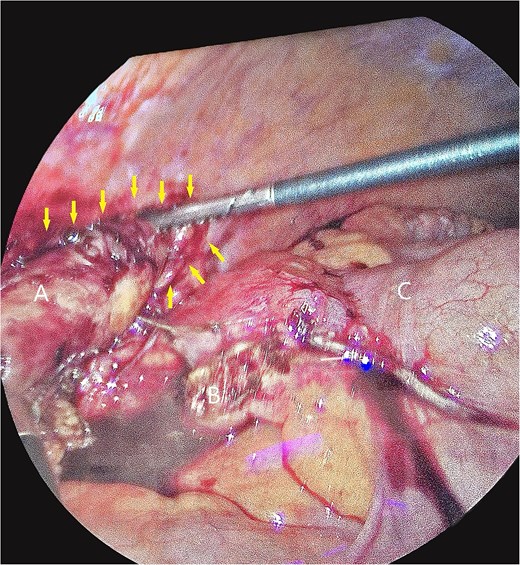

The patient underwent laparoscopic appendectomy with laparoscopic enterolysis. The appendix appeared inflamed, dilated, and gangrenous, with a perforation located 2 cm from the base. Notably, the appendix was not in a retrocecal position as initially suspected but was found to be herniating through a defect in the iliacus muscle (Fig. 3). The appendix was circumferentially freed from the hernia defect, which was identified as tracking cephalad between the iliacus muscle and the iliac bone. The hernia defect measured 2.5 cm and was primarily closed using two figure-of-eight 2–0 Vicryl sutures, leaving a small inferior opening to allow for drainage (Fig. 4). A 19 Fr Blake drain was placed in the right lower quadrant and paracolic gutter.

Intra-operative photos of appendix contained within iliacus hernia after appendix was divided. The arrows showcase the hernia with appendix. (A) Appendix, (B) mesoappendix after division, (C) cecum with staple line.

Iliacus hernia defect closed primarily after appendix was removed.